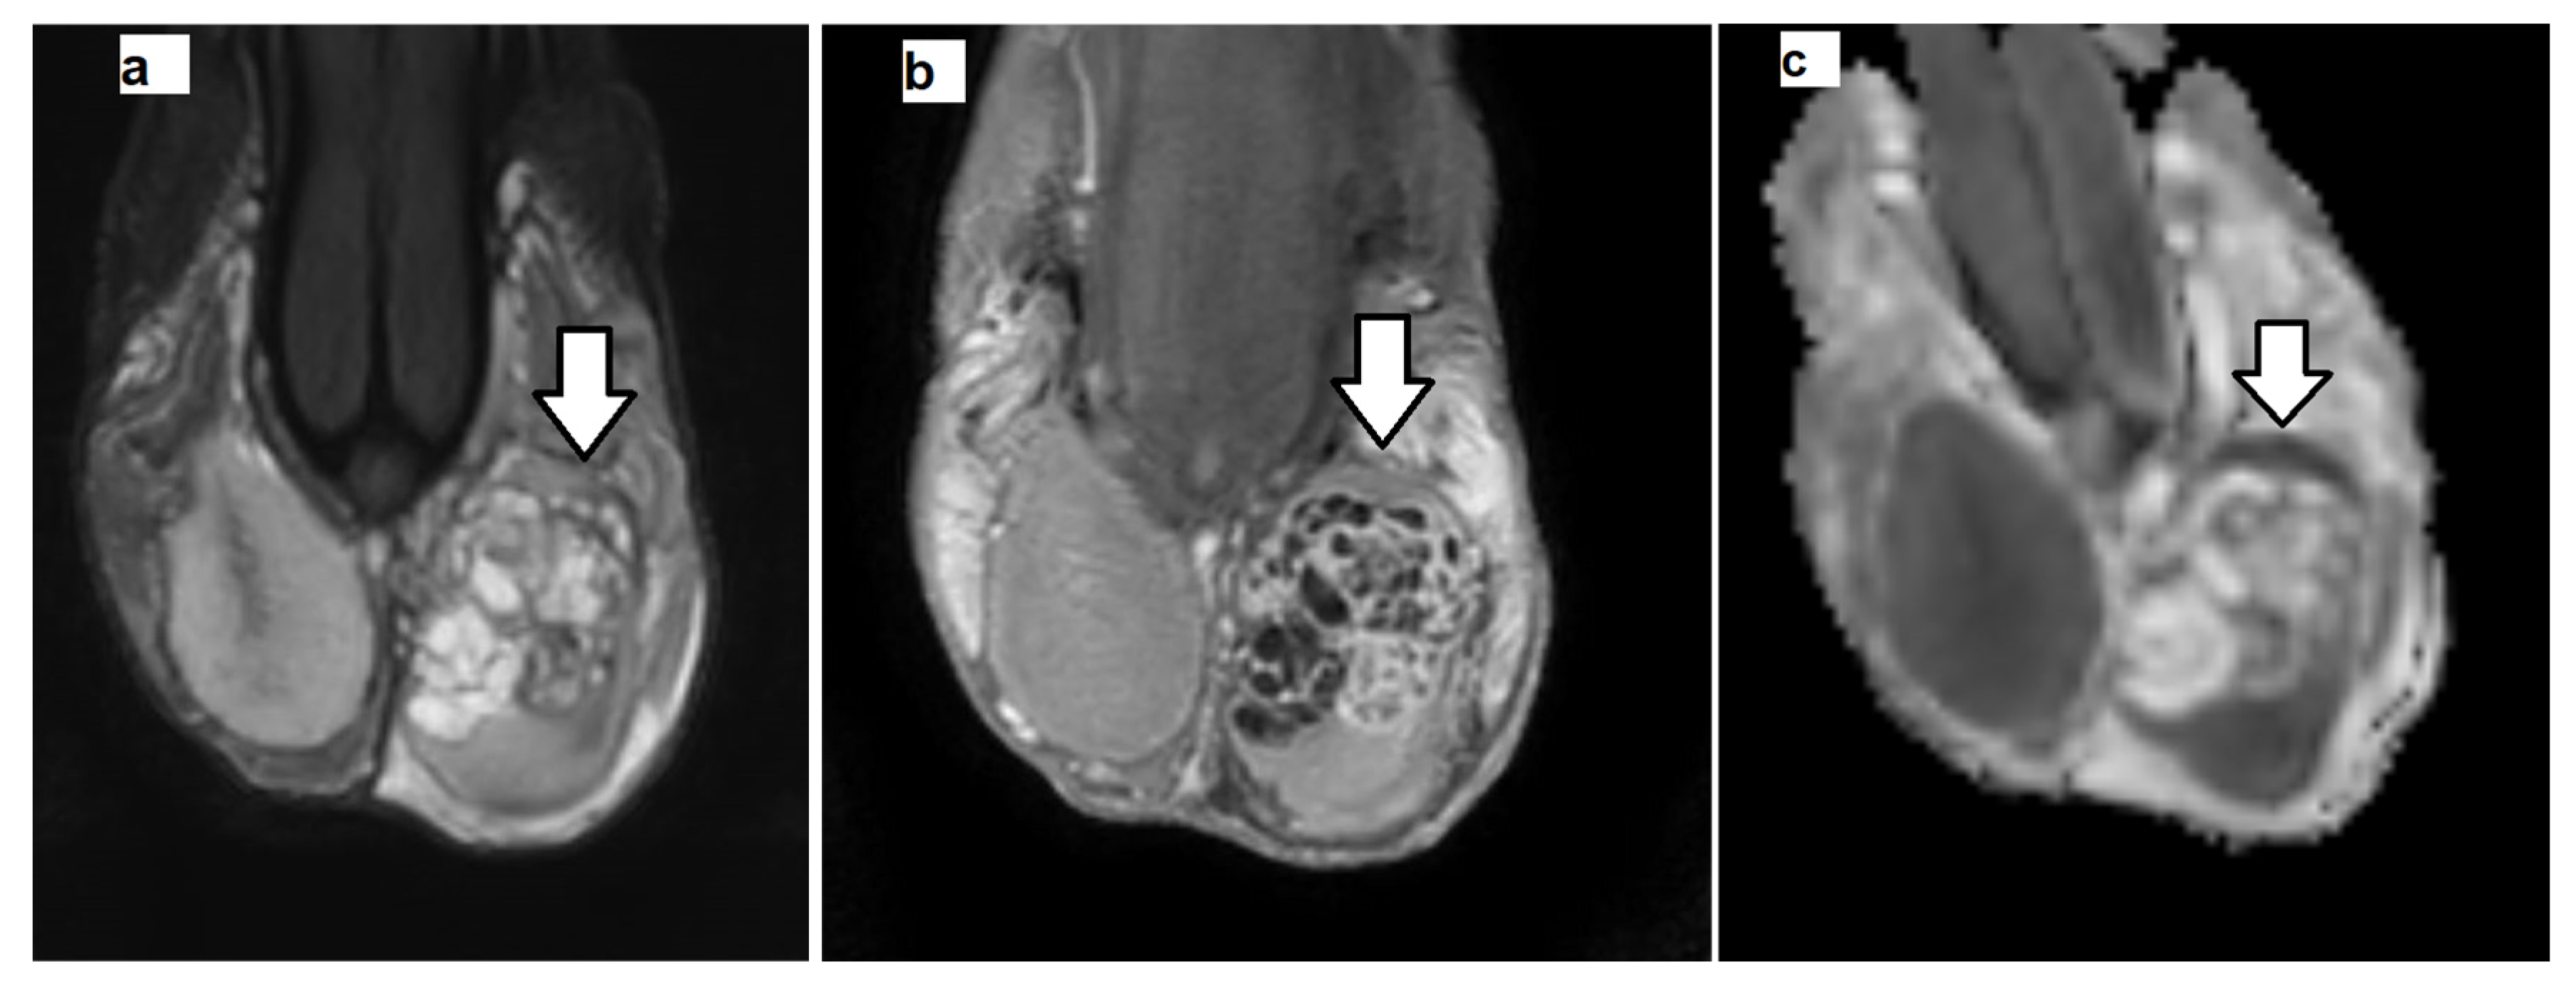

2.3. MRI Data Postprocessing

2.4. Histologic Evaluation